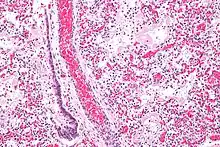

На рентгенографії легень видно двобічні дифузні інфільтрати, іноді — плевральний випіт. Такі ознаки неспецифічні й також характерні для кардіогенного набряку легень, що ускладнює диференціальну діагностику[15][16]. Комп'ютерна томографія показує негомогенну інфільтрацію легень у деяких відділах (у задньонижних відділах у лежачих хворих)[17]. Це пояснюється тим, що розподіл набряку легень залежить від сили тяжіння, а також тиском з боку розташованих вище набряклих відділів легень[18].

Бронхоальвеолярний лаваж — найнадійніший метод діагностики ГРДС. Під час нього вводять гнучкий фібробронхоскоп в один з уражених сегментів легенів. Потім промивають легеневий сегмент ізотонічним розчином і аналізують склад промивної рідини[5]. У хворих з ГРДС виявляють нейтрофіли, що становлять 60-80 % всіх клітин промивної рідини (в нормі < 5 %)[19].